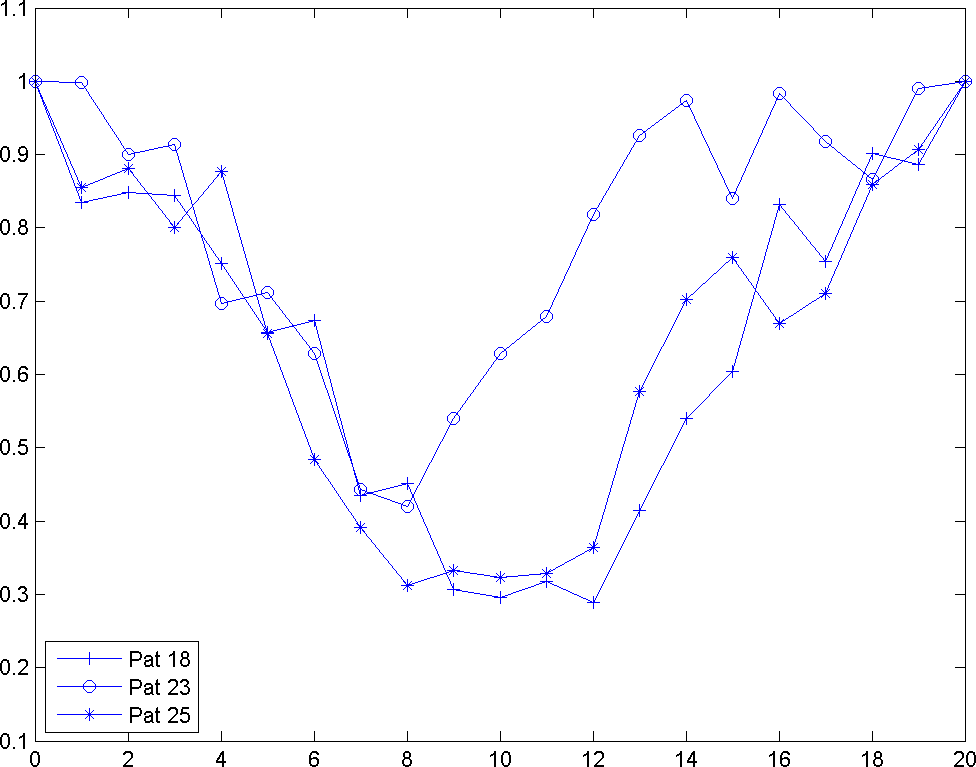

4.2 Analysis of Volumetric Changes in Left Ventricle

Analysis of volumetric changes of left ventricle in cardiac cycle can be helpful in understanding the process of heart muscle’s deformation. Also, it helps us study the effects of infarction on the heart’s performance. For this analysis, the data provided for inner contours of left ventricle is used to approximate the volume. In order to better understand the process and reduce the errors caused by the differences in the sizes of left ventricle of patients, the computed volumes are normalized with respect to the initial volume in the beginning of systole. Fig. 7 displays the normalized graphs of volumetric changes for the three aforementioned patients.

The first difference that is noticeable comparing these graphs is between frames 0 to 3. In this region the healthy subjects, 18 and 25, show a small decrease followed by a two frame rest. There is a delay in patient 23 due to inactive regions in the heart muscle. On the other hand in patient 23 the minimum volume is 42% of the maximum volume which for healthy subjects this minimum volume is about 30% (31.66% for patient 25 and 28.86% for patient 18). This is also due to the existence of infraction and the effect of loading and wasting energy caused by them.

The other difference is that in the unhealthy subject the diastole starts sooner. To be specific, in 18 and 25 there is a rest region between frames 9-12 and 8-12 respectively. For 23 this region is limited between frames 7-8. It can be inferred that this effect is caused by the residual stress and inertial effects of inactive regions. Although the analysis of volumetric changes can help to distinguish between the healthy and unhealthy heart muscle, it doesn’t provide any information about the location of MI.